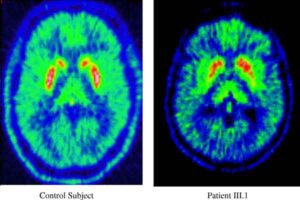

Per la prima volta un gruppo di scienziati del Center for Cognitive Brain Imaging della Carnegie Mellon University ha utilizzato...

I deficit cognitivi successivi ad una commozione cerebrale risultano ancora presenti dopo due mesi dall'evento traumatico secondo una nuova ricerca...